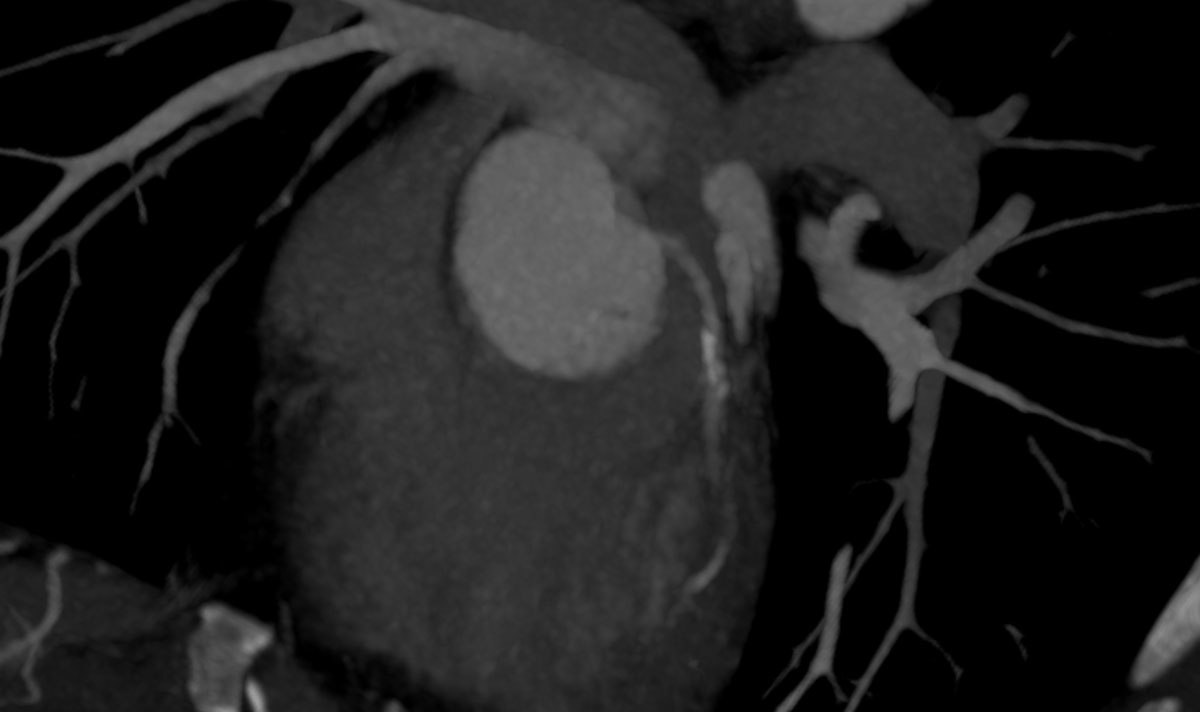

A total of 85/200 patients (42.5%) exhibited incidental findings requiring immediate further medical workup and/or treatment. Of note, most incidental findings here were newly diagnosed cardiovascular conditions, with coronary artery calcification being the most prevalent finding followed by arterial aneurysms and incidentally detected embolism (table 2, figs 1, 2a and 2b ). Pancreatic and liver tumours were less frequent, but significant. Examples of incidentally diagnosed tumours are shown in figures 3 and 4 .

Figure 1 Axial CT scan of the left coronary artery in a 43-year old ED patient showing coronary artery calcification which led to a coronary angiogram.

Most of the findings considered to require immediate treatment were related to CAC. CAC was seen on CT scans in over 37.5% of ED patients. Thus, coronary atherosclerosis was incidentally diagnosed in more than 20% of patients in our study. According to the American College of Radiology, assessing the presence of CAC on CT scans may be valuable to the patient and referring physician, either for reassurance that no CAC is present or to increase patient awareness of coronary heart disease risk, and to stimulate discussion and further workup of cardiac risk factors [17]. Thus, based on these findings, a significant number of previously asymptomatic patients may have had an additional benefit from the CT scan performed for workup of ED.